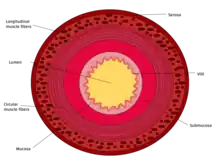

This cross section diagram shows the 4 layers of the small intestine wall.

The three sections of the small intestine look similar to each other at a microscopic level, but there are some important differences. The parts of the intestine are as follows:

Muscularis externaLongitudinal and circular layers, with Auerbach's (myenteric) plexus in betweenSame as duodenumSame as duodenum

SubmucosaBrunner's glands and Meissner's (submucosal) plexusNo BGNo BG

Mucosa: muscularis mucosaeNormalNormalNormal

Mucosa: lamina propriaNo PPNo PPPeyer's patches

Mucosa: intestinal epitheliumSimple columnar. Contains goblet cells, Paneth cellsSimilar to duodenum, but the intestinal villus is longSimilar to duodenum, but the intestinal villus is short